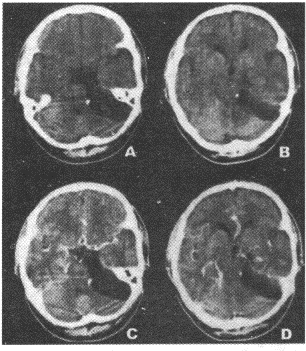

13.女性,43歲。左側(cè)面部不適感1年。CT圖像如圖所示,需要進行鑒別診斷的疾病包括

正確答案:AD 解題思路:膽脂瘤為起源于外胚層的先天性腫瘤,是胚胎早期神經(jīng)溝封閉時,皮膚外胚層的剩件留下來發(fā)展而成。

14.男性,8歲。頭痛伴噴射狀嘔吐2個月。

正確答案:AB